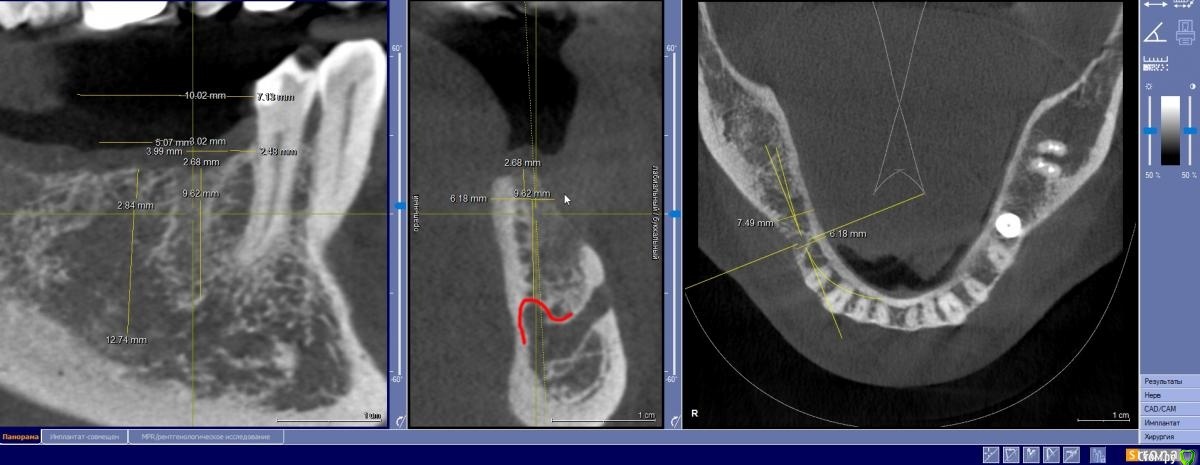

zumanok Опубликовано 15 февраля, 2021 Поделиться Опубликовано 15 февраля, 2021 Коллеги достаточно часто встречаюсь с такой картинкой на КТ в области ментального отверстия . Считаете ли вы это частью тройничного нерва или не обращать внимания? Ссылка на комментарий

Doctor Vlad Опубликовано 15 февраля, 2021 Поделиться Опубликовано 15 февраля, 2021 Коллеги достаточно часто встречаюсь с такой картинкой на КТ в области ментального отверстия . Считаете ли вы это частью тройничного нерва или не обращать внимания там что угодно может быть, больше похоже на пору кости. в этом случае до канала далеко. вы же не собираетесь так глубить? Ссылка на комментарий

zumanok Опубликовано 15 февраля, 2021 Поделиться Опубликовано 15 февраля, 2021 (изменено) там что угодно может быть, больше похоже на пору кости. в этом случае до канала далеко. вы же не собираетесь так глубить?Интересно может быть такая форма канала или стоит взять винт подлиньше? Примерно так и собирался, мб на пол мм выше. Объясните пожалуйста почему не стоит? Кроме того что коронка на 1 мм подлиньше будет. Изменено 15 февраля, 2021 пользователем zumanok Ссылка на комментарий

Doctor Vlad Опубликовано 16 февраля, 2021 Поделиться Опубликовано 16 февраля, 2021 Интересно может быть такая форма канала или стоит взять винт подлиньше? Примерно так и собирался, мб на пол мм выше. Объясните пожалуйста почему не стоит? Кроме того что коронка на 1 мм подлиньше будет.скорей всего там нерва нет и это не канал. Но. А если есть)? Ссылка на комментарий

zumanok Опубликовано 16 февраля, 2021 Поделиться Опубликовано 16 февраля, 2021 (изменено) скорей всего там нерва нет и это не канал. Но. А если есть)?Да вот,для этого и выбрал 3.5 на 8.5. Сам склоняюсь к тому что костный рисунок, информации о таком строении нерва не нашел. Думаю в процессе препарирования ложа посмотреть, если будет чувствительность то не лезть дальше.Подскажите чем Вас смутила глубина установки имплантата? Только этим образованием?По КТ 1.5мм до него. Изменено 16 февраля, 2021 пользователем zumanok Ссылка на комментарий

Raystom Опубликовано 16 февраля, 2021 Поделиться Опубликовано 16 февраля, 2021 Там будет не чувствительность, а резкий провал фрезы после определенного момента препарирования, если не отслеживать момент с глубиной, чем напугаете и себя и пациента. По поводу рисунка может быть как и костный рисунок, так и петля нижнелуночкого канала, зачем проверять? Ссылка на комментарий

Doctor Vlad Опубликовано 16 февраля, 2021 Поделиться Опубликовано 16 февраля, 2021 Да вот,для этого и выбрал 3.5 на 8.5. Сам склоняюсь к тому что костный рисунок, информации о таком строении нерва не нашел. Думаю в процессе препарирования ложа посмотреть, если будет чувствительность то не лезть дальше.Подскажите чем Вас смутила глубина установки имплантата? Только этим образованием?По КТ 1.5мм до него.как он нарисован норм, длиннее не стал бы, чтобы запас был. Просто, по вашим фото не совсем видно где канал. иногда и по кт все очень смутно. особенно когда огромные поры. Ссылка на комментарий

Nazim_NV86 Опубликовано 16 февраля, 2021 Поделиться Опубликовано 16 февраля, 2021 Просто пора. Меня больше размер 3.5-8.5 смущает. Я бы отогнул вогнутую вестибулярную часть и поставил. Заодно и десны мб накинул. Ссылка на комментарий

zumanok Опубликовано 16 февраля, 2021 Поделиться Опубликовано 16 февраля, 2021 (изменено) Там будет не чувствительность, а резкий провал фрезы после определенного момента препарирования, если не отслеживать момент с глубиной, чем напугаете и себя и пациента. По поводу рисунка может быть как и костный рисунок, так и петля нижнелуночкого канала, зачем проверять?Благодарю за ответ. Проверять не собираюсь, ставить буду по шаблону поэтому и выбрал этот размер что бы не задеть. Но решил уточнить правильно ли я делаю или все таки таких вещей не стоит остерегаться. как он нарисован норм, длиннее не стал бы, чтобы запас был. Просто, по вашим фото не совсем видно где канал. иногда и по кт все очень смутно. особенно когда огромные поры.Длиннее не буду. Спасибо. Но все таки докопаюсь до Вас . Чем Вас смутило само заглубление? Очень глубоко? Просто пора. Меня больше размер 3.5-8.5 смущает. Я бы отогнул вогнутую вестибулярную часть и поставил. Заодно и десны мб накинул. Меня немного тоже. Думал поставить 4х8.5 но как то совсем в притык получается. Параллельно в области 4.6 буду ставить 4,5х10 планирую их спаять. Поидее проблем быть не должно. ССТ у 4.5.вестибулярно. Изменено 16 февраля, 2021 пользователем zumanok Ссылка на комментарий

Nazim_NV86 Опубликовано 17 февраля, 2021 Поделиться Опубликовано 17 февраля, 2021 Меня немного тоже. Думал поставить 4х8.5 но как то совсем в притык получается. Параллельно в области 4.6 буду ставить 4,5х10 планирую их спаять. Поидее проблем быть не должно. ССТ у 4.5.вестибулярно.1. Смотря какая протетика потом будет. Если будет абатмент без 6гр оригинал( хоть винтовую делайте на нём), то не парьтесь - ставьте 3.5 и связывайте. Если всякая дребедень, типа премилов, оснований, то рискуете увидеть перелом шейки. Тогда см. 22. Базальная часть челюсти весьма широкая. Тут даже НКР+имплант на ура зайдёт. Как я уже писал, отогнуть фрагмент и поставить хоть 4.5 можно. Это мой субъективный опыт. Ссылка на комментарий

Doctor Vlad Опубликовано 18 февраля, 2021 Поделиться Опубликовано 18 февраля, 2021 Но все таки докопаюсь до Вас . Чем Вас смутило само заглубление? Очень глубоко? не то что бы я так не делал))) но глубоковато. мое мнение. опять же в связке с другим имплантом рычаг будет компенсирован 1 Ссылка на комментарий